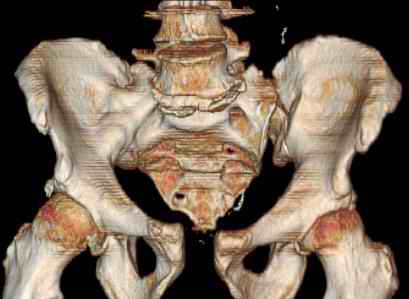

Was hemodynamic unstable at local ER, sent to our Trauma center where circumferential pelvic binder placed and pt. stabilized with fluid, blood, and rewarming. Angiography not performed. An extraperitoneal bladder disruption was found, uro elected to treat non-operatively. Initial xray (not shown) demonstrated 5-7 cm wide at symphysis and SI joint. The first image attached is of CT once binder is in place.

On post trauma day 5 the pt was taken to OR for ORIF of his iliac wing fracture and SI dislocation. The swelling/3rd spacing of fluid in the area of symphysis was profound, but quite acceptable posteriorly.

Patient was prone for procedure, as I thought too difficult to fix the wing in lateral position. Of course the repair of wing was easy, but reduction of SI very demanding. The Floro images document the residual lack of reduction. That was the closest I could get it using 6mm joystick in wing, and clamp on sacrum and clamp through notch. The fixation was (initially) rigid. Anterior ex fix with supra-acetabular pins was placed due to condition of soft tissues, massive "beer-belly" overhanging the crest.

Post trauma day ten patient's xray shows failure of posterior construct. Plan was to perform revision orif once soft tissues resolve considerably for full anrterior fixation and posterior fixation. However, while Im away for holiday (on Post trauma day 15), pt is developing septic clinical appearance, and trauma suspects pelvic abcess near symphysis and performs I and D - finds nothing but no primary closure performed. Posterior tissues/incision continue to look healthy. Now is post trauma day 17, pt is still tubed/on dopamine/and wbc still elevated, anterior incision still packed open.